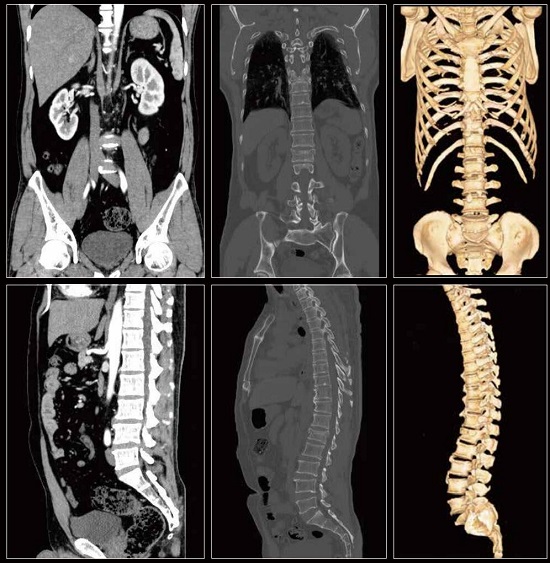

Features: - A high-end 32-slice CT with Optimal Resolution - Professional & Accurate, Delicate & Comprehensive - Low Dose Technology - Super-fast workflow - One-key intelligent Scanning - High-Speed Reconstruction System